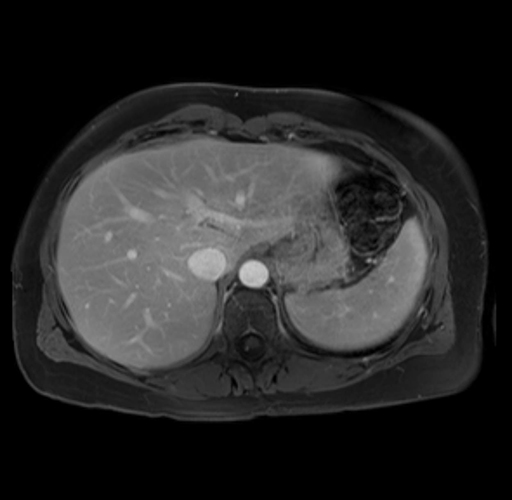

Imaging Analysis

Look through the patient's CT scan to identify any areas of concern for the necessary procedure.

Based on your CT findings, which issue(s) are present and would give reason for "planned slowing down moment(s)" in this case?